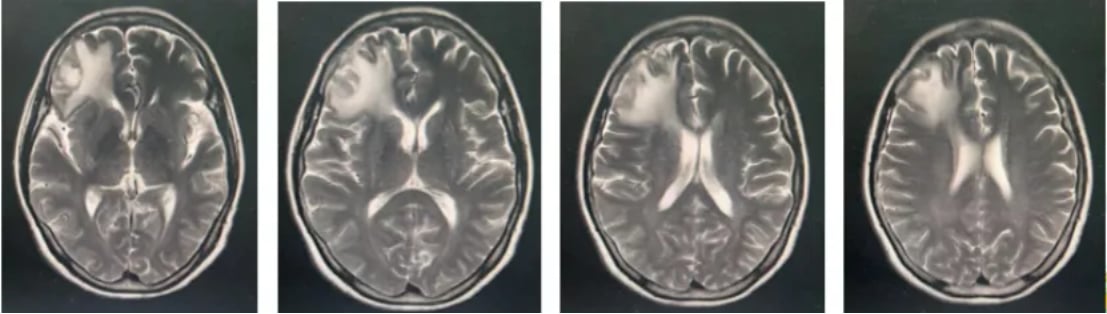

面对棘手的病情,医生同样采用了基于替尼泊苷的联合化疗方案。在第一个疗程后,患者出现了粒细胞缺乏伴发热的副作用,医生及时将后续化疗剂量减少了25%。经过调整后的3个疗程治疗,患者的症状显著改善,复查影像显示病灶缩小,同样达到了部分缓解(PR)。

这个病例说明,即使对于年龄较大且出现较严重不良反应的患者,通过适当调整剂量,替尼泊苷方案依然能够安全、有效地控制疾病。如果您对治疗方案或副作用管理有疑问,可以咨询MedFind的AI问诊服务。